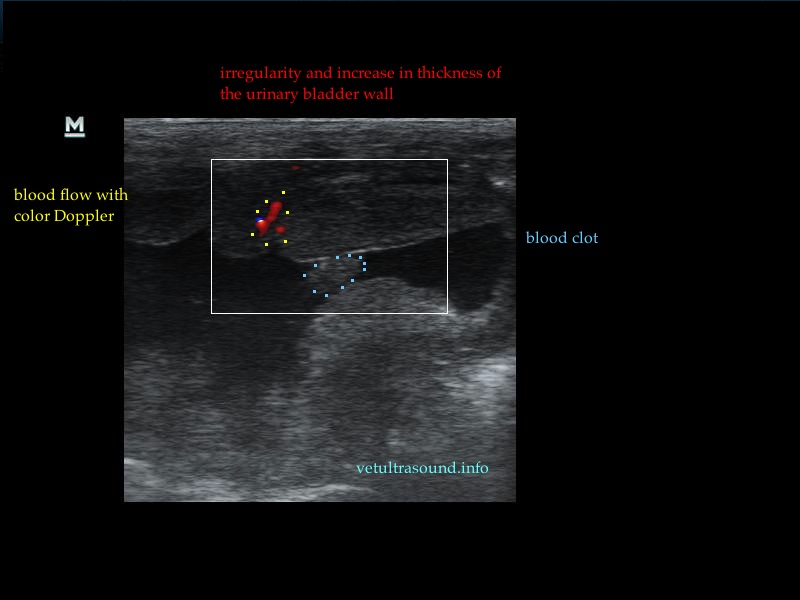

Η πάχυνση του τοιχώματος και η δοκίδωση του βλεννογόνου είναι εμφανής σε όλες τις εικόνες. Πολλές φορές οι λαγόνιοι λεμφαδένες μπορεί να είναι ήπια διογκωμένοι και να έχουν αντιδραστική ηχομορφολογία. Ο έλεγχος με έγχρωμο Doppler του τοιχώματος της άδειας κύστης μπορεί να μας δείξει ροή αίματος στα αγγεία της κύστης. Αντίθετα, είναι πιθανό, όσο η κύστη γεμίζει με ούρο η ροή αίματος να μην είναι ορατή με το Doppler. Αυτό συμβαίνει συχνά στη χρόνια βακτηριακή κυστίτιδα λόγω της ίνωσης του τοιχώματος της ουροδόχου και αυτή είναι μία από τις αιτίες της μη ανταπόκρισης στη θεραπεία. Η συγκεκριμένη παθοφυσιολογία έχει μελετηθεί στον άνθρωπο με την βοήθεια ενδοσκοπικού υπερήχου.

The increase of thickness of the urinary bladder wall and the striation of the mucosa is evident. Inguinal lymphnodes are usually prominent and mildly enlarged. Colour Doppler may reveal the blood flow of the mucosa of the empty urinary bladder, whereas the blood flow in a full bladder appears decreased. This could be because of the fibrosis of the urinary bladder wall and could explain why sometimes chronic conditions like these do not respond well to antibiotics. This pathophysiology has been studied in humans with the use of endoscopic ultrasound.

– Evaluation of blood flow in the mass with colour/power Doppler

– The mass should invade the mucosa (if we can see the mucosa enclosing the neck of the mass)